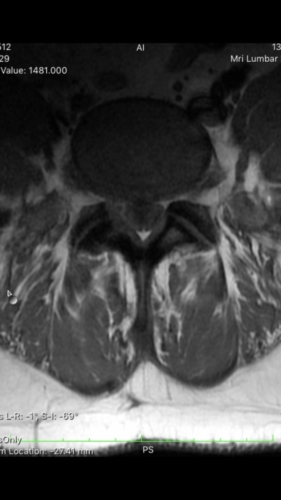

I had spinal surgery on my L4-L5 disc years ago because it was herniated and causing me to be unable to walk. The surgery went well but now I'm having issues on and off with my legs again. They go numb often and sometimes it will last for 5min or so before I can move. I went for an MRI recently to see what was going on and they sent me home w the images. I have a decent idea of what I am looking at but would appreciate some clarity. I'm not quite sure what my spine looked like after surgery so not certain what is considered normal in this case since it's been worked on. Could you please help me read my MRI? Thanks so much!

a couple more images.